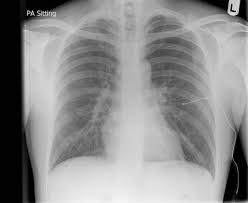

Pneumothorax

Pneumothorax from www.saem.org

Hover on/off image to show/hide findings. Finding of pneumothorax on chest radiographs may include the following: Typical abg findings in pneumothorax include low pao 2 and low paco 2 (due to hyperventilation). A pneumothorax refers to the presence of gas or air in the pleural space. This may occur because of a number of reasons and may be spontaneous. The video is an effort to revisit the pneumothorax. Pneumothorax describes gas within the pleural space. Schematic illustration of the radiographic findings and differences between pneumothorax and artifacts related to skinfolds.

Tap on/off image to show/hide findings. This is the one not to miss. Please see disclaimer on my website www.academyofprofessionals.com Patients will not always be symptomatic and treatment will depend on the cause. On an expiration film, the pneumothorax will be more evident because on expiration, there is less lung air, therefore, the lungs will look whiter, making the density difference between the pneumothorax and the lungs more evident, and the size of the pneumothorax will appear larger. Hover on/off image to show/hide findings. Tap on/off image to show/hide findings. Physical examination of patients with tension pneumothorax is usually remarkable for tracheal deviation, decreased chest expansion, increased percussion note, decreased breath sounds, and neck veins distension. Ultrasound imaging also may be used to identify a pneumothorax. Patients with a larger pneumothorax may have decreased movement of the chest wall, a positive coin test result, diminished fremitus, or decreased to absent breath sounds on the affected side. The condition spans all age groups, and ems providers should, therefore, maintain a high index of suspicion for pneumothorax for any patient with a. Hover on/off image to show/hide findings. Pneumothoraces may be small or very large.